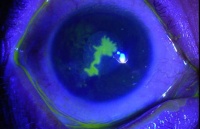

角膜瘢痕: 当角膜溃疡达到洁净期后,角膜内结缔组织增生,修复缺损,溃疡愈合,形成瘢痕。溃疡小而浅仅累及上皮细胞层者,角膜可以完全恢复透明。如果前弹力膜和角膜实质浅层受累,则遗留致密混浊的瘢痕。混浊初则暗淡,继则浓度增加,但永远不会越过溃疡边缘。角膜瘢痕的消失仅限于乳儿,年龄稍大则不可能,必然遗留永久的瘢痕,从而引起视力障碍。在瘢痕开始形成而被破坏部分尚未完全恢复原来的弯曲度,但荧光素已不着染,角膜上形成一小凹,名为角膜小面。最终小面消失,角膜恢复正常的弯屈度。但也有个别病例的角膜小面永久不变。

角膜瘢痕的大小和厚薄按溃疡轻重而有所不同,薄者混浊浅在,名角膜云翳,稍厚者名角膜斑翳,最厚而致密者名角膜白斑。

角膜瘘并非一瘘管,乃是一疏松组织嵌在角膜破孔内,房水从裂缝渗出。角膜瘘最容易发生在瞳孔边缘嵌顿在角膜穿孔区域内的患者。房水经常沿瞳孔缘外渗,上皮细胞不易进行修复。由此可知,角膜瘘的主要病征为角膜表面有深黑色之隆起、前房消失和眼球变软等现象。此外,还可用荧光染色证明。